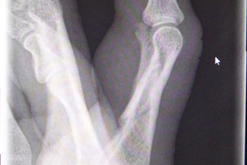

Wegen eines verbliebenen Rotationsfehlers des rechten Ringfingers wurde der Klägerin anderenorts eine Korrekturoperation empfohlen (s. Abb.3

3. In den postoperativen Röntgenkontrollen sei die radiale Abweichung des rechten Ringfingers erkennbar, die einen Drehfehler ohne gesicherten Hinweis nicht ganz ausschließen ließe.

5. Die Fraktur sei in Fehlstellung ausgeheilt. Aus den vorliegenden Dokumenten würde nichthervorgehen, welche weiteren Therapieoptionen diesbezüglich in Anspruch genommen seien.